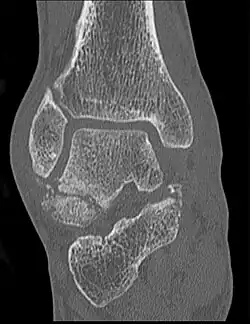

Die Verletzung stellt sich mit Schmerzen und Schwellung in der Fußwurzel und außen am Fuß dar. Diese Befunde können leicht mit einer Verstauchung, Zerrung oder einem Bänderriss am Außenknöchel verwechselt werden. Dieses insbesondere, wenn nicht bekannt ist, dass es sich um einen Snowboarder handelt. Auch ist der Knochenbruch auf Übersichtsröntgenbildern manchmal schwer zu erkennen. Eine Computertomographie kann die Bruchlinien überlagerungsfrei darstellen und ist für die Planung der richtigen Therapie hilfreich.[6][14][7][12]